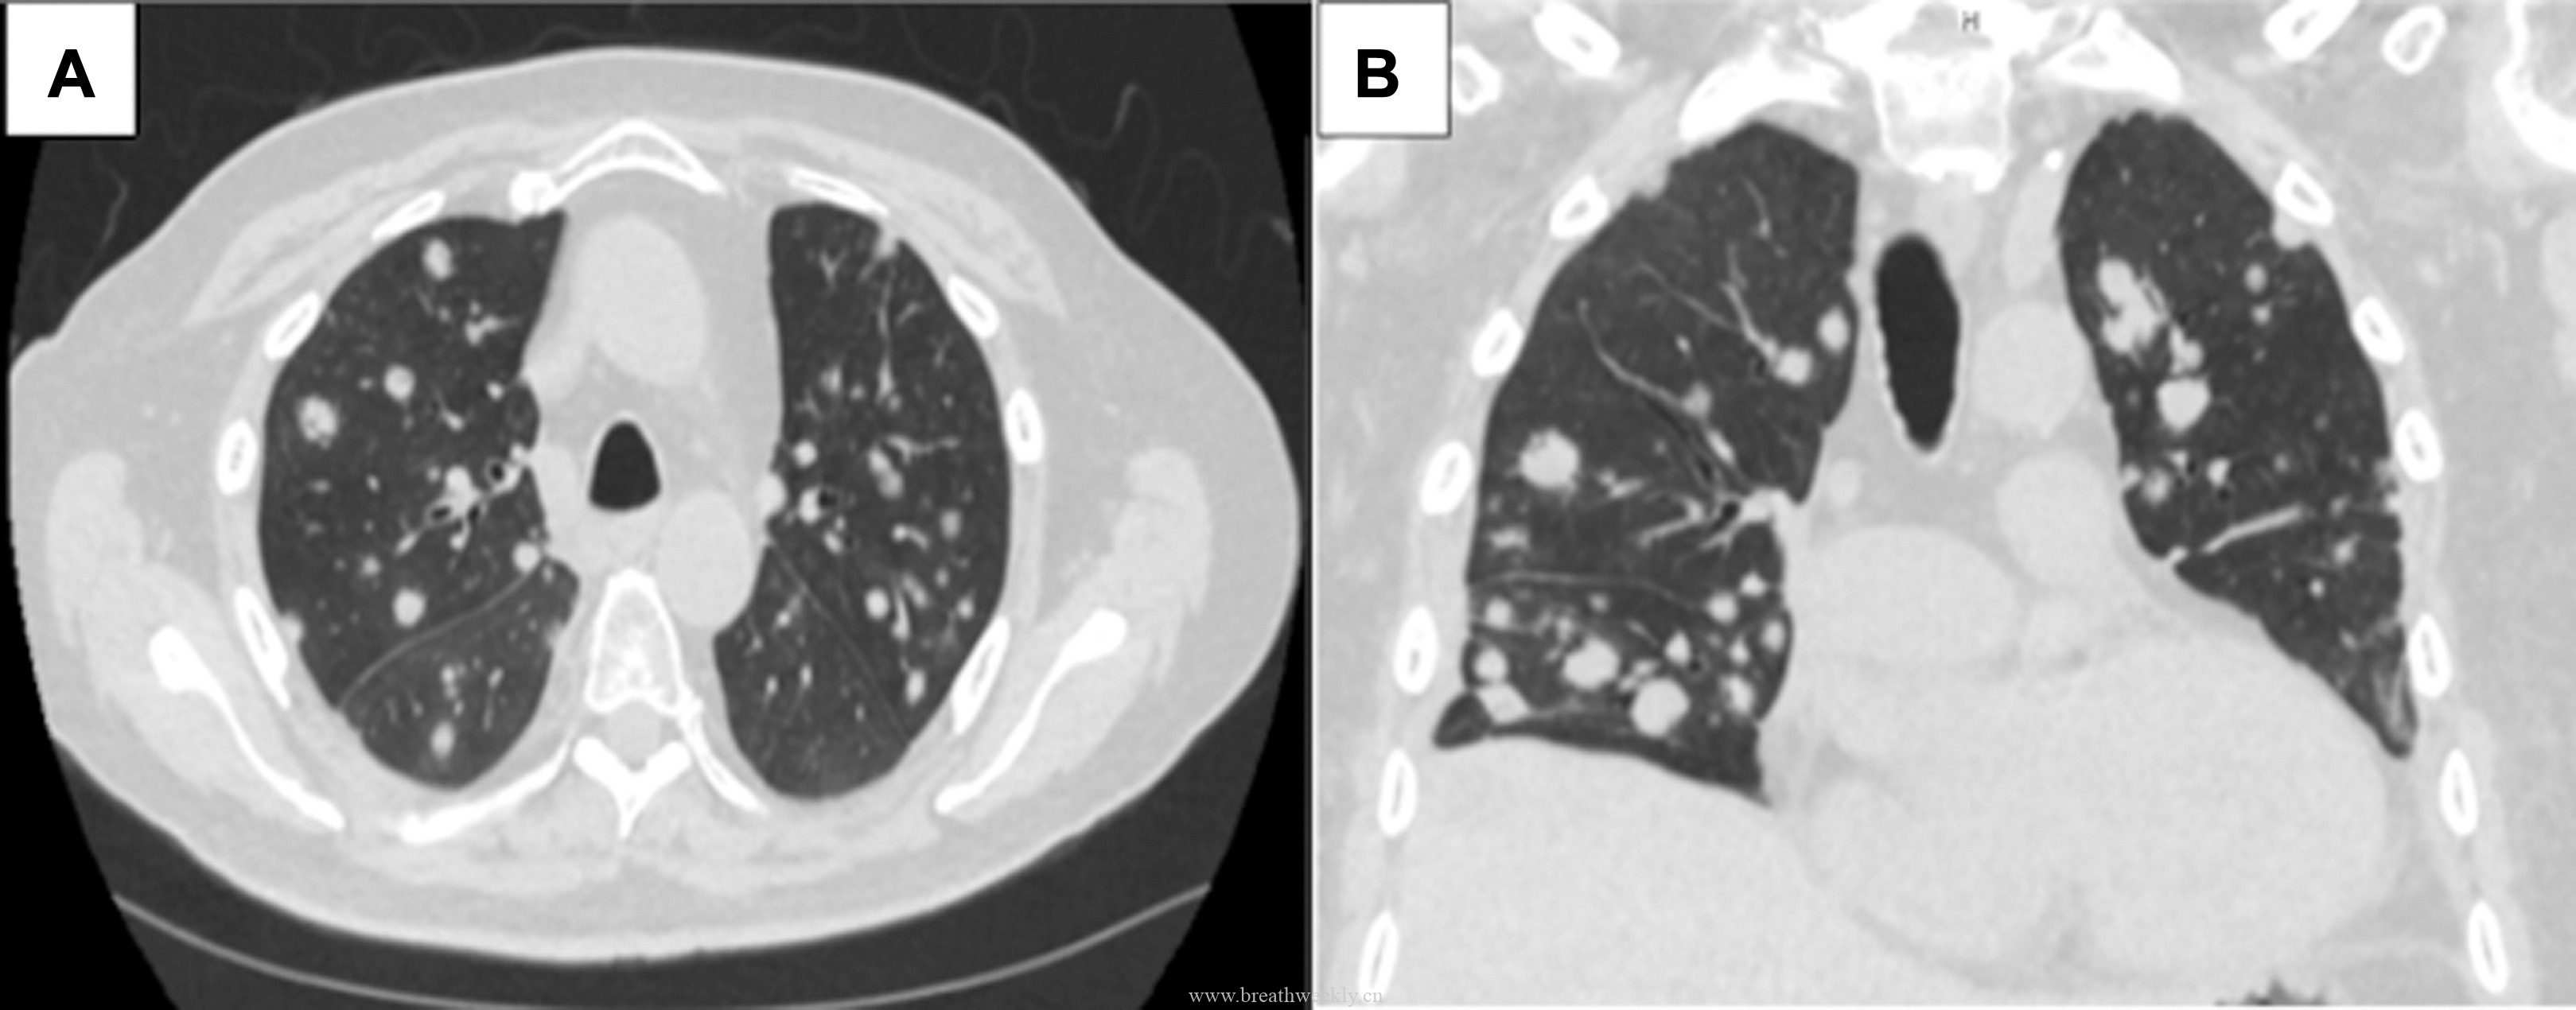

影像学检查

头颅CT除外颅内肿块及脑出血。脑及颈椎MRI(增强)除外CT隐性病灶,但发现右侧胸廓入口处囊性病灶。颈部超声及增强胸部CT:右侧上纵隔囊性占位,位于甲状腺右叶后下方,内见结节性实性成分及上极供血血管。胸部CT示前纵隔预期胸腺位置无异常软组织,提示胸腺脂肪萎缩。

⁹ᵐTc – 甲氧基异丁基异腈甲状旁腺显像:早期及延迟图像均可见甲状腺右叶下方异常摄取灶,摄取位于右上纵隔囊性病灶的实性成分内。